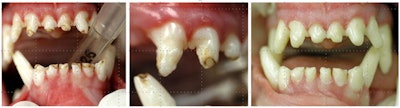

Figure 1: Periodontal conditions in a dog. All images courtesy of Larry Kimberlin, DVM.

Figure 1 is a digital dental x-ray demonstrating bone loss and periodontal pocketing, which have allowed bacteria to reach the root and cause an abscess. Greater than 50% of the normal bone structure has resorbed. These teeth cannot be salvaged and must be extracted. Unlike most general practice veterinarians, Dr. Kimberlin fills extraction sites with either a synthetic bone replacement material, or a homologous bone graft material that has recently become available to place in the socket, then the gingiva is sutured over it to allow rapid healing and prevent pain when eating.

Willie Nelson (yes, that's really his name), a Catahoula Leopard dog commonly used for herding cattle, suffered from distemper as a puppy. Willie was one of the lucky 1% that survives distemper, but as a result he now has enamel dysplasia (just as children do after some infections). The weakened enamel has a mottled appearance and is susceptible to chipping.

Figure 2A and 2B illustrate the preoperative conditions showing enamel defects. In this case, the teeth were minimally prepared back to sound tooth structure then restored with Amelogen Universal composite (Ultradent). Figure 2C shows the final result with a nice, highly polished surface.